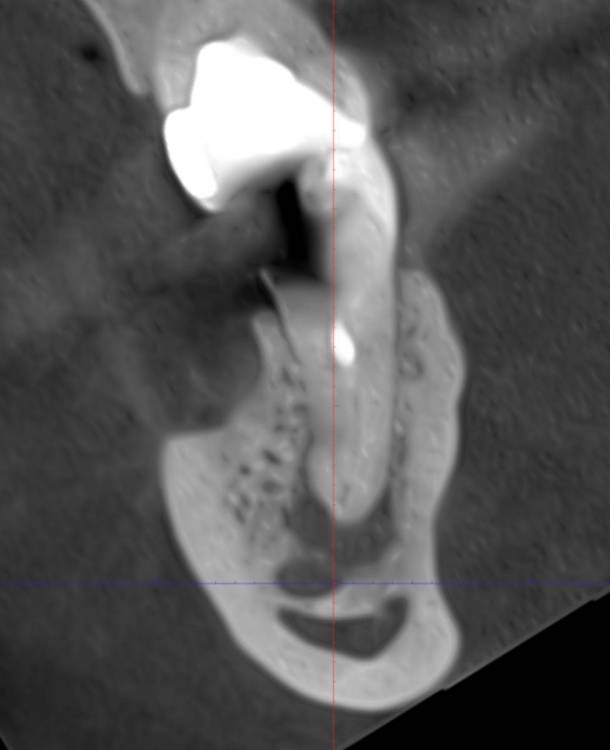

safroxa Опубликовано 7 марта, 2023 Автор Поделиться Опубликовано 7 марта, 2023 Здравствуйте уважаемые доктора. Лечу зубы. Дошла до нижней семёрки справа. Ситуация такая: канал проходит слишком близко к нерву. Доктор посоветовал удалить и поставить имплант. Есть ли шанс, все же залечить каналы и спасти зуб? Ссылка на комментарий

safroxa Опубликовано 17 марта, 2023 Автор Поделиться Опубликовано 17 марта, 2023 Еще раз здравствуйте, дорогие доктора. Обратилась с вопросом о нижней семерке справа к другому врачу. Сказал, что попробует помочь, но гарантий нет. На днях залечила 6-ку (рядом), врач сказал, что на него необходима тоже коронка. Скажите пожалуйста, если не удастся спасти 7-ку, нужен ли будет имплант на его место или достаточно коронки на 6-ке? Снимок еще раз прилагаю. Хорошего ортопеда в нашем городе найти сложно. Ссылка на комментарий

Doc Опубликовано 17 марта, 2023 Поделиться Опубликовано 17 марта, 2023 Есть шансы у этого зуба или нет, сказать может только тот врач, который возьмется. Чаще всего есть, но далеко не всегда. Если удалить и не протезировать, то верхняя семерка со временем, скорее всего, начнет сдвигаться в низ и блокировать движение нижней челюсти. Это не очень хорошо. Так что лучше поставить имплантат, тем более, что кость там вполне хорошая. 1 Ссылка на комментарий